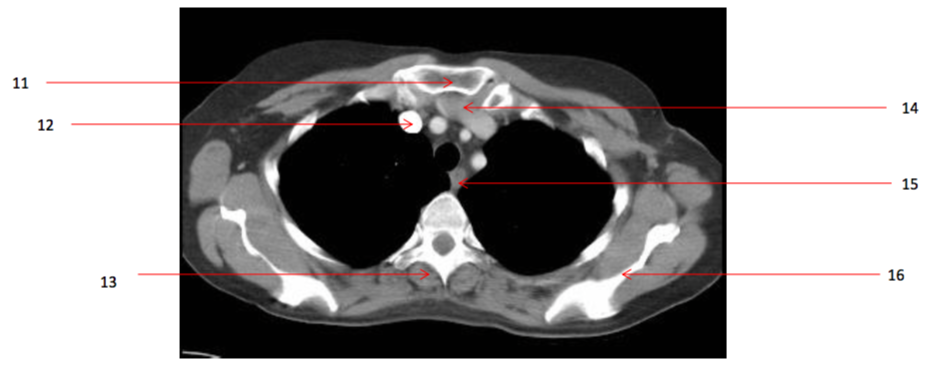

Number 13?

Rt erectae spinae muscle

Number 16?

Lt scapula

Number 14?

Lt brachiocephalic vein

Number 11?

Sternum (manubrium)

Number 12?

Rt brachiocephalic vein